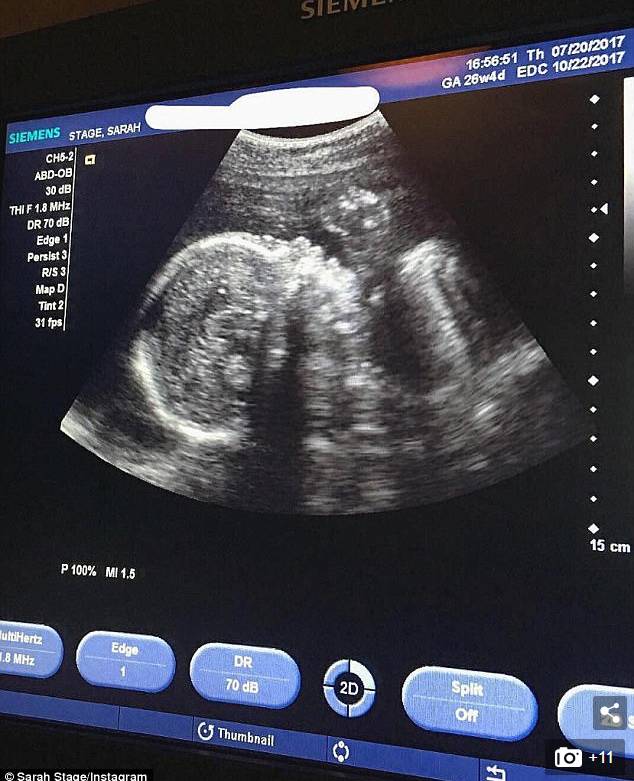

各种评论让Sarah也很无奈,上周四Sarah发布了一张超声波照片。

Sarah的超声波照片

宝宝已有2磅重了,心跳强劲有力,身体很健康